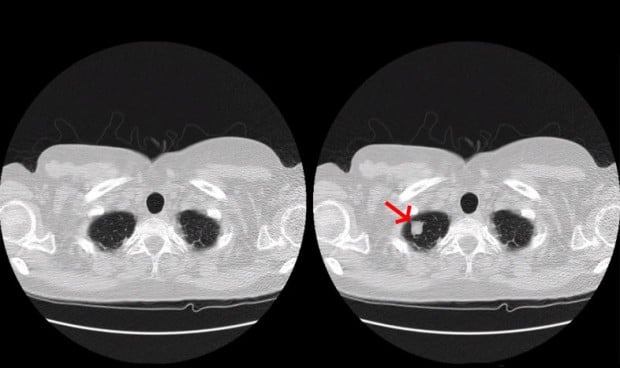

Concretamente, tras alterar hasta 70 tomografías, el equipo ha logrado mentir a tres radiólogos expertos en test ciegos puesto que lo que ataca el malware es la imagen que envía el tac al profesional. En el caso de tumores fabricados, los radiólogos identificaron cáncer el 99 por cientos de las ocasiones, y en el caso de que los signos de cáncer fueran eliminados de pacientes que sí lo padecían, los radiólogos fueron engañados en el 94% de las veces.

El estudio abarca ejemplos de cáncer de pulmón, pero un ataque como el que imagina este malware funcionaría igualmente para tumores cerebrales, enfermedades cardiacas, coágulos sanguíneos, lesiones de la columna vertebral, lesiones de ligamentos, artritis y fracturas óseas.